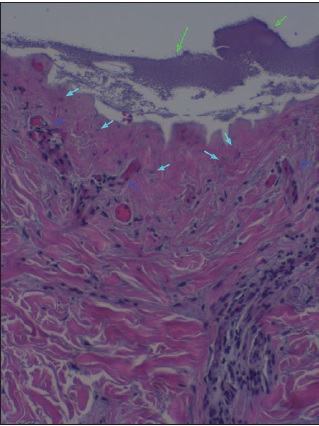

La realización de biopsias pre y postratamiento en 3 de los pacientes permitió observar 2 casos de desbridamiento parcial de la zona necrótica, siendo 1 caso una quemadura de tercer grado en dorso de mano que precisó de injerto (Fig. 25 a 34, caso 9), y el otro una quemadura previamente tratada con Flammazine Cerio® (Fig. 35 a 45, caso 12). En el tercero de los pacientes biopsiados apreciamos desbridamiento histológico completo de la zona necrótica con preservación de la dermis sana (Fig. 46 a 50, caso 11). Como hallazgos significativos, en las 3 muestras postratamiento evidenciamos un infiltrado inflamatorio linfocítico perivascular (Fig. 36, 40 y 48).

Otro hallazgo significativo de nuestro estudio es el incremento del infiltrado inflamatorio tras el tratamiento (Fig. 36, 40 y 48). Sin embargo, no podemos afirmar que sea consecuencia del tratamiento enzimático ya que no realizamos comparación con zonas de quemadura no sometidas a tratamiento con Nexobrid®. Además, en la literatura existe referencia al infiltrado neutrofílico típico que existe en la zona intermedia de la quemadura (región histológica comprendida entre la zona sana y la zona necrótica de la quemadura), pero el evidenciado en nuestro estudio es un infiltrado linfocítico perivascular que, hasta donde nosotros sabemos, no aparece mencionado en ningún estudio publicado sobre el desbridante Nexobrid®.(21) Aunque desconocemos si este infiltrado es originado o potenciado por el tratamiento con Nexobrid® o bien debido exclusivamente a la progresión de la quemadura, sería necesario estudiar si el posible incremento del infiltrado inflamatorio guarda correlación con la velocidad de curación o con el pronóstico a largo plazo, o bien es únicamente el resultado de la evolución fisiopatológica de la quemadura y no existen diferencias con el infiltrado evidenciado en las quemaduras no tratadas con Nexobrid®.